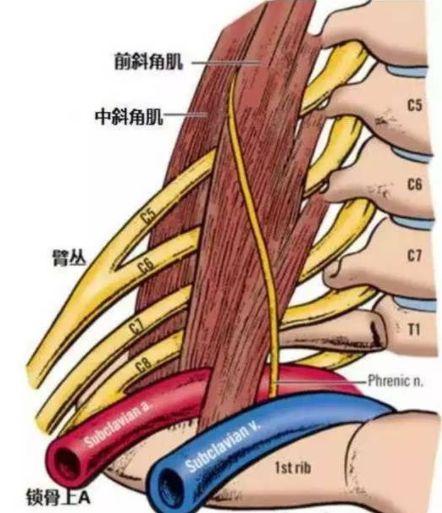

指の知覚神経は頸髄から神経根に分かれ、頸部腋窩で腕神経叢を形成し、上腕と前腕を通って橈骨神経、正中神経、尺骨神経となり、手と指に分布する末梢神経となる。

頚髄神経根を分割し、頸部に形成する。腕神経叢分ける橈骨神経、正中神経、尺骨神経経絡は上腕と前腕を等距離に通過し、最終的に頚椎となる。末梢神経手と指に分布している。そのため、指先のしびれは必ず上記の神経に問題がある。

3.上腕神経の損傷

腋窩や前頸部は病変や損傷の影響を受けやすく、尺骨神経、正中神経、屈筋神経の全体的または部分的な損傷が混在していることがある。治療の原則は以前と同じである。

頚椎の肥大や過形成、頚椎椎間板の変性やヘルニアは、頚神経根や頚髄を圧迫し、片側または両側の手指のしびれや痛みを誘発し、それが次第に上腕や前腕に進展し、上肢の運動障害にまで至ることがある。

如中高年特に指先のしびれ。夜間就寝中に悪化する多くは頚椎症が原因である。頚椎症は中高年に多い。骨棘頚椎症の場合、夜寝ている間に肥大した骨によって頚椎神経が圧迫刺激を受け、それが症状を引き起こす。

また、正中神経も尺骨神経も、首の脊髄から枝分かれした神経で形成されている。そのため、頚神経が出てきて尺骨神経と正中神経に分かれる時期に、何らかの圧迫があると手指のしびれも起こりますが、このようなしびれは、手指のしびれだけでなく、腕などのしびれも伴うのが普通で、圧迫される場所としては、首の前斜角筋と中斜角筋の位置が最も多く、胸郭出口症候群と呼ばれています。

頚椎症、骨棘、椎間板ヘルニアなどは、脊髄から枝分かれする神経根が詰まりやすく、詰まると手のしびれも起こり、手のしびれは胸郭出口症候群と同じような症状が現れます。しかし、手のしびれによって引き起こされるこの症状は、より明らかな頚椎の不快感、こわばり、痛み、活動制限があるでしょう。

5.頚椎症

頚椎症は頚椎が突出する長期的な要因により、両側の神経や血管を圧迫し、指のしびれの主な原因は神経から腕神経叢神経や頚神経を圧迫することであるため、腕神経叢神経損傷や頚神経叢神経損傷だけでなく、上肢の神経の損傷も指のしびれの原因となります。